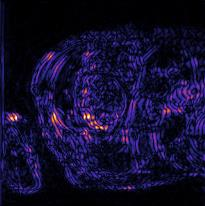

Recently, deep neural networks have greatly advanced undersampled Magnetic Resonance Image (MRI) reconstruction, wherein most studies follow the one-anatomy-one-network fashion, i.e., each expert network is trained and evaluated for a specific anatomy. Apart from inefficiency in training multiple independent models, such convention ignores the shared de-aliasing knowledge across various anatomies which can benefit each other. To explore the shared knowledge, one naive way is to combine all the data from various anatomies to train an all-round network. Unfortunately, despite the existence of the shared de-aliasing knowledge, we reveal that the exclusive knowledge across different anatomies can deteriorate specific reconstruction targets, yielding overall performance degradation. Observing this, in this study, we present a novel deep MRI reconstruction framework with both anatomy-shared and anatomy-specific parameterized learners, aiming to "seek common ground while reserving differences" across different anatomies.Particularly, the primary anatomy-shared learners are exposed to different anatomies to model flourishing shared knowledge, while the efficient anatomy-specific learners are trained with their target anatomy for exclusive knowledge. Four different implementations of anatomy-specific learners are presented and explored on the top of our framework in two MRI reconstruction networks. Comprehensive experiments on brain, knee and cardiac MRI datasets demonstrate that three of these learners are able to enhance reconstruction performance via multiple anatomy collaborative learning.